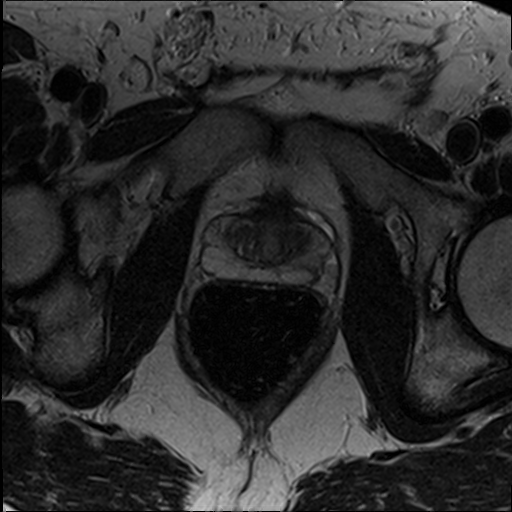

The Conditional Random Field as a Recurrent Neural Network layer is a recently proposed algorithm meant to be placed on top of an existing Fully-Convolutional Neural Network to improve the quality of semantic segmentation. In this paper, we test whether this algorithm, which was shown to improve semantic segmentation for 2D RGB images, is able to improve segmentation quality for 3D multi-modal medical images. We developed an implementation of the algorithm which works for any number of spatial dimensions, input/output image channels, and reference image channels. As far as we know this is the first publicly available implementation of this sort. We tested the algorithm with two distinct 3D medical imaging datasets, we concluded that the performance differences observed were not statistically significant. Finally, in the discussion section of the paper, we go into the reasons as to why this technique transfers poorly from natural images to medical images.